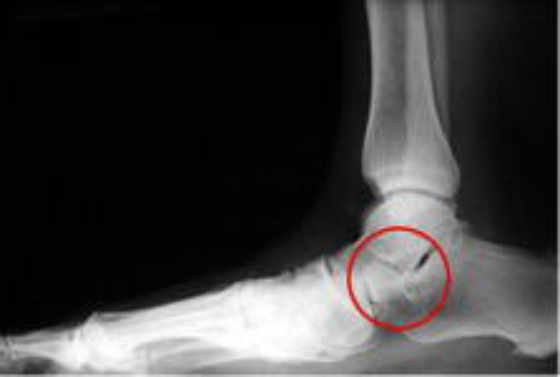

Radiografía lateral con implante colocado correctamente en pie plano flexible

Implante HyProCure™ en pie plano flexible

Implante HyProCure™